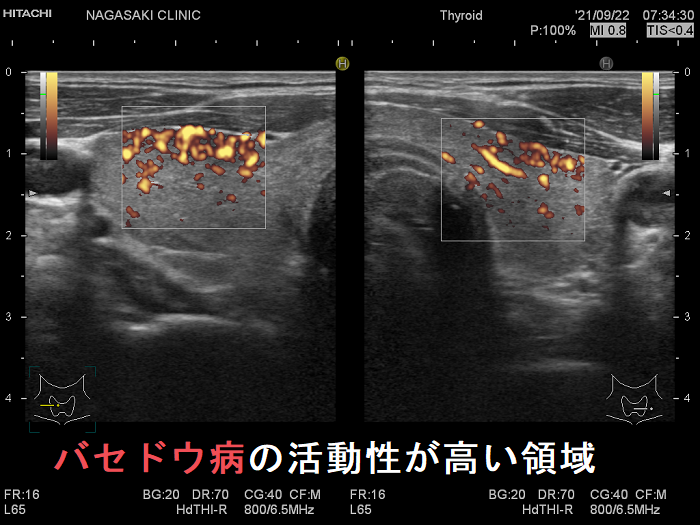

局所的に血流が多く、低エコーな領域

抗甲状腺薬投与により、甲状腺機能が正常に保たれているバセドウ病では、治療前の”火炎状血流増加”と呼ばれる甲状腺内部の異常血流増加が減少していきます。しかし、局所的に血流が多く、低エコーな領域は活動性が残存しています。(J Clin Ultrasound. 2005 Oct;33(8):381-5. doi: 10.1002/jcu.20157.)(Exp Clin Endocrinol Diabetes. 2013 Jan;121(1):1-5.)(AJR Am J Roentgenol. 1996 Jan;166(1):203-7.)

局所的に血流が多く、低エコーでバセドウ病の活動性が高い領域

局所的に血流が多く、低エコーでバセドウ病の活動性が高い領域  ドプラーモード

バセドウ病 局所的に活動性が高い部位

バセドウ病 局所的に活動性が高い部位(低エコー)

バセドウ病 局所的に活動性が高い部位 ドプラーモード

バセドウ病 局所的に活動性が高い部位 ドプラーモード(低エコー領域は局所的に血流が多く)